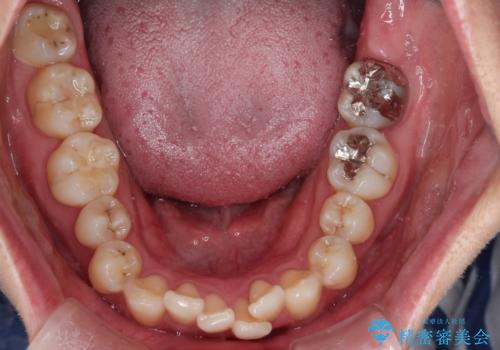

- 前歯のでこぼこが気になると来院されました。

奥歯の噛み合わせは綺麗に噛んでいたため、前歯の叢生(でこぼこ)を、短期間で治療完了するように計画しました。

奥歯の噛み合わせは整っていたため、前歯の並びを美しく修正することに専念できました。マウスピース矯正による治療で短期間で改善しました。